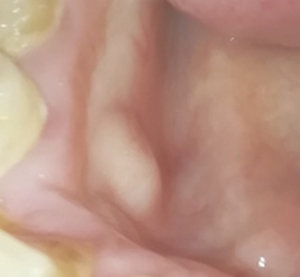

Подскажите, пожалуйста. Болела десна около недели, незначительно. Позже образовался какой-то шарик, похожий на прыщик. А после, во время еды что-то стало мешать и вот появилось непонятное новообразование из десны. На ощупь твердое, беспокоит во время приема пищи.

Подскажите, что это может быть?

Очень сложно определить, но все Ваши симптомы говорят и свищевом выходе. То есть, на верхушках зуба имеется воспалительный процесс.

Необходимо обратиться к врачу, сделать рентген-снимки и выявить точную причину.